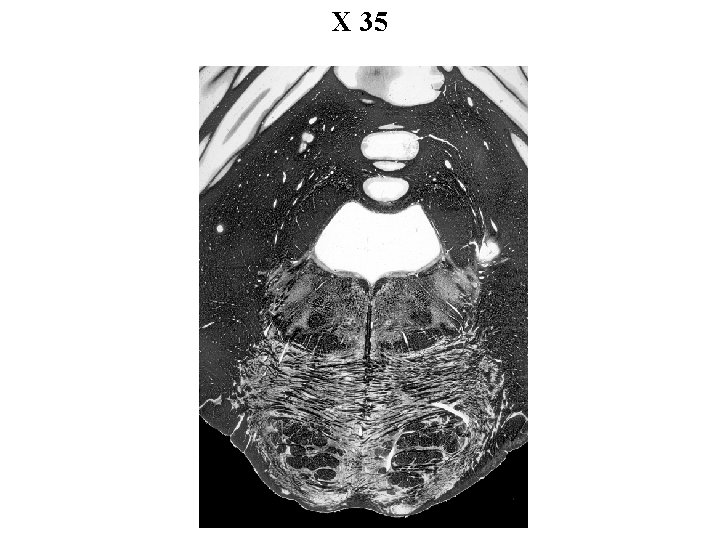

X 35